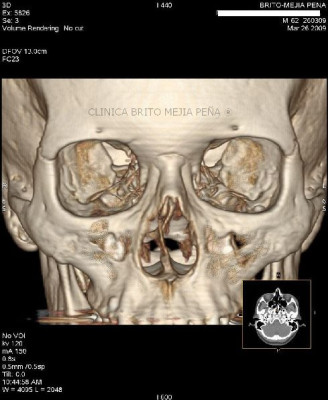

Fractura malar